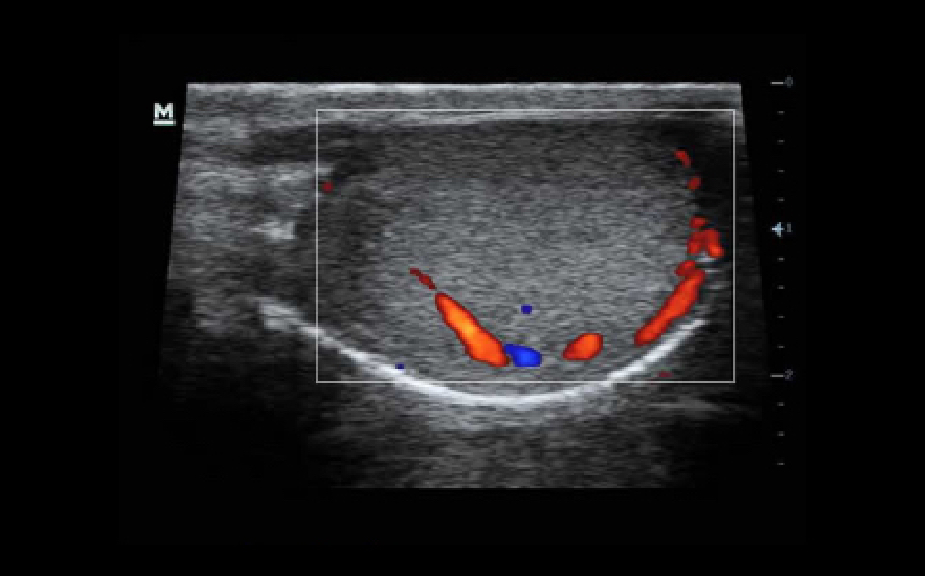

Y├╝ksek performans, kapsaml? klinik uygulamalar ve entegre tasar?m?n nihai kombinasyonu ile Z50, daha h?zl? ve etkili yan?t vermenize yard?mc? olacakt?r. Siyah Beyaz sistemden, y├╝ksek d├╝zeyde verimli Renkli Doppler sistemine ge?i? art?k her zamankinden daha kolay ve basit ve hasta bak?m? s?z konusu oldu?unda s?n?rlar?n ?tesine ge?mek ve s?radanl??? a?mak art?k m├╝mk├╝n.

iScape?

Taramay? daha kolay, ak?c? ve kontrol edilebilir hale getiren velosite g?sterimi ve ileri/geri tarama imkan? ile birle?tirilmi? panoramik g?r├╝nt├╝leme tekni?iyle, anatomik yap?n?n b├╝t├╝n ve geni? g?r├╝nt├╝s├╝n├╝ elde edin.

ExFOV

Anatomik yap?n?n geni? g?r├╝nt├╝s├╝ sayesinde t├╝m konveks ve lineer problar ile daha iyi tan? bilgisi elde edin.